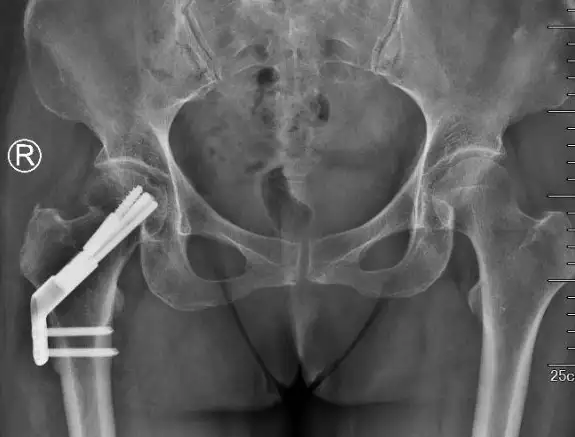

FNS